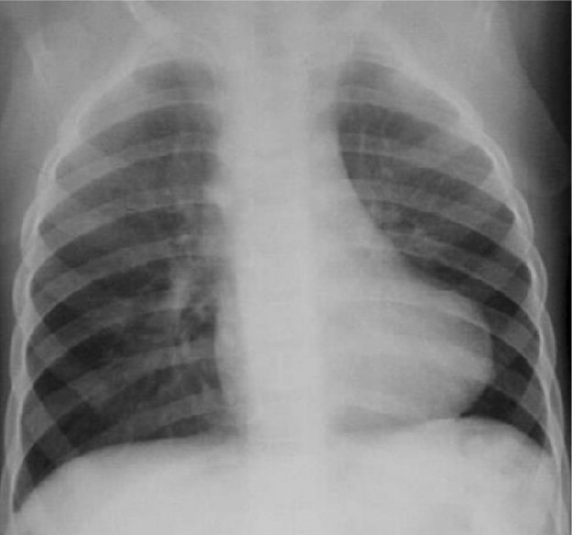

Chest radiograph

Chest radiograph is the first radiological examination and has a classical “cor-en-sabot” appearance, reduced pulmonary vascularity, and absent pulmonary bay (Figure 1). It has poor sensitivity, and the characteristic findings may be seen only in severe cases, typically in later stages. Moreover, it may be used to monitor changes after corrective surgery. Post-repair chest radiographs may show cardiac enlargement and heterogeneity in pulmonary vascular distribution[15]. Bedside chest radiographs can also help identify and follow up complications such as pleural effusion in the immediate post-operative period, particularly in the intensive care unit.

Figure 1

Figure 1  Frontal chest radiograph of a child who presented with cyanotic spells showing a boot-shaped heart (cor-en-sabot) with upturning of the cardiac apex, pulmonary oligemia, and absence of the pulmonary bay.